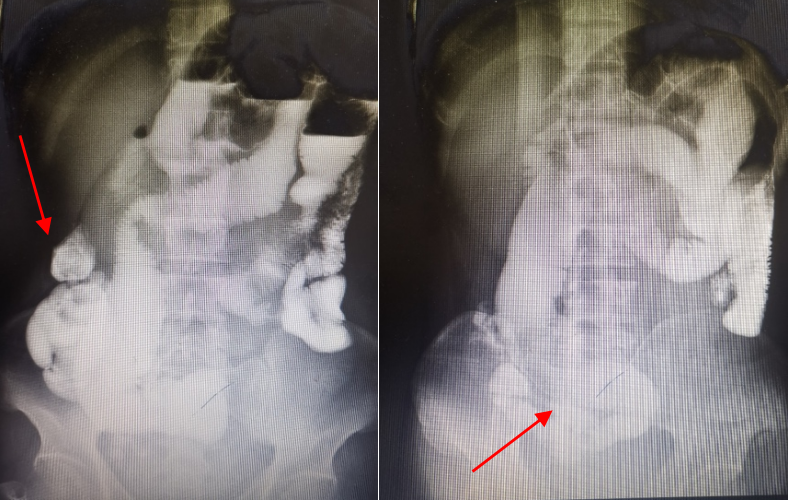

术前造影图

术后诊断:直肠低分化腺癌T3N2M0 Dukes’C期。术后予以同步放化疗,自辅助治疗期间起患者腹盆腔CT提示骶前出现炎性病变,并逐渐进展。与此同时,患者开始出现无明显诱因造口停止排气排便,保守治疗后可好转,但此状况反复发生。至本次就诊时,患者半年内体重下降5kg。患者腹部查体可见腹部稍膨隆,左下腹造口袋见少量气体,听诊肠鸣音稍亢。会阴部陈旧伤口凹陷,见一大小0.2cm窦道外口。入院后完善PET/CT提示:骶前不规则软组织影考虑治疗后炎性肉芽肿病变可能大,恶变不除外,病变与双侧输尿管下段粘连致双侧输尿管扩张积液;腹膜后淋巴结转移。经MDT讨论诊断肠梗阻+放射性肠炎(会阴部感染窦道)+肿瘤复发?,拟行腹腔镜下肠粘连松解+肠切除吻合(备肠排列术)。

对于内科治疗无效的放射性肠炎的并发症,常需手术治疗。这类并发症包括肠梗阻、肠瘘、肠穿孔、肠出血、肿瘤和营养不良。放射性肠炎的手术具有复杂性,术前应通过影像学检查(如:非出血患者——CT、钡剂造影和MR;出血患者——内镜)尽可能明确定位病变。此外,术前经常放置输尿管支架以保护输尿管,并标记造瘘口的位置,确保造瘘口位于放射野之外。